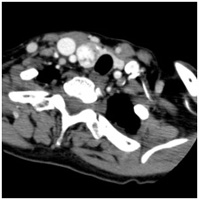

急性腹症の原因や腹部臓器原発の悪性腫瘍の検索

占拠性病変の有無や鑑別診断,腹部内臓器やリンパ節への進展度や転移の確認など